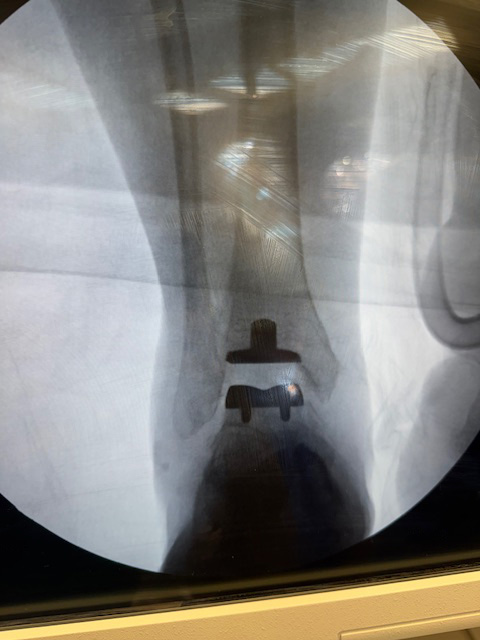

"Surgical misadventure" by another surgeon about 8 years ago. The wrong fixation was used for a flatfoot repair, & the deformity was not corrected. Patient came in with severe foot & ankle pain, with no arch at all. She was unable to play with her grandchild because the pain was so bad, & because she felt unsteady. The old hardware was removed, a lateral calcaneal lengthening osteotomy was performed along with a medial column/1st ray realignment. The ankle was painfully arthritic, & patient elected a total ankle replacement vs. an ankle fusion. She is now able to walk pain free & play with her grandchildren!